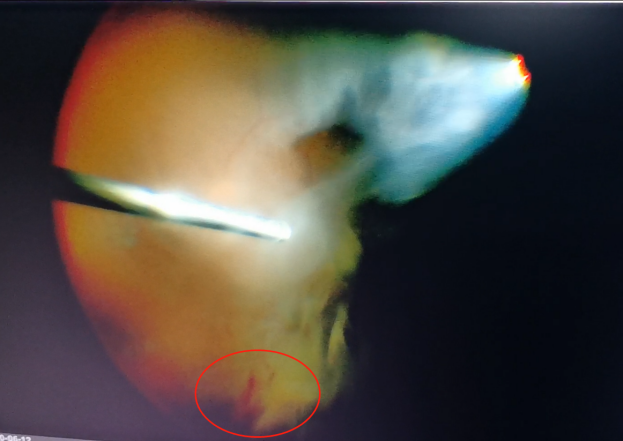

手術中,醫(yī)生們先后為程先生行白內(nèi)障超聲乳化術及后入路玻璃體切割術,并置入人工晶體。手術僅用半個小時便順利完成。

(左為玻璃體切割術中,明顯可見有積血;右為激光治療后的眼底)

術后第二天視力檢查時,程先生經(jīng)過手術的左眼矯正視力已經(jīng)恢復為1.0,眼前也不再有“黑片片”遮擋視線。恢復了清晰“視界”的程先生,開心地自己在病房外來回溜達。